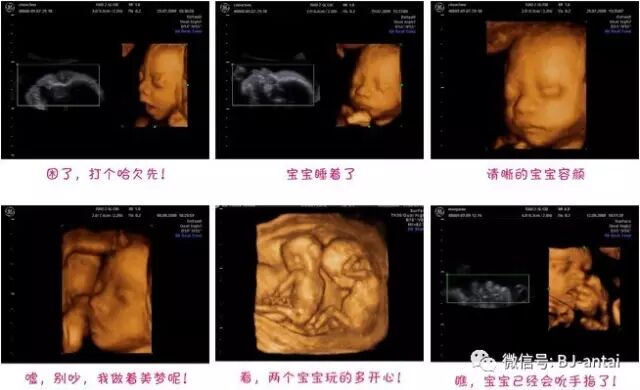

四维视频观赏:

安太妇产四维彩超动态图,团购地址: